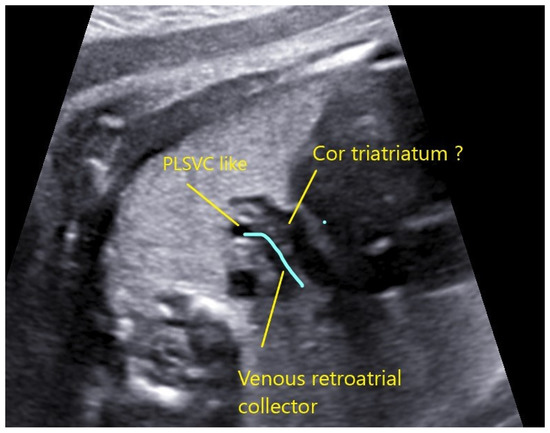

4.2. Case 2